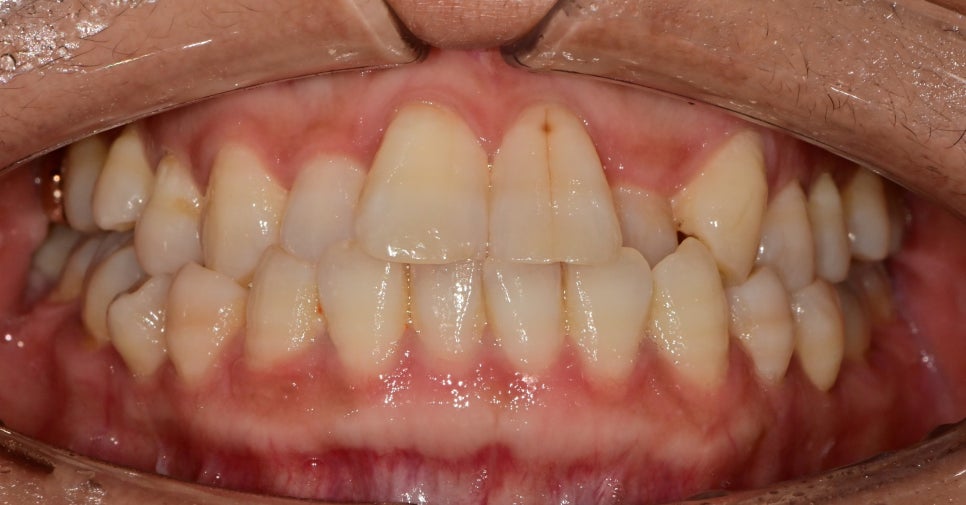

크랙라인이 생긴 앞니 치료

가운데 대문니에 수직적인 크랙 라인이 관찰됩니다.

환자분은 처음에 이것을 목적으로 내원하신 게 아닌

스케일링 및 관리를 받으러 오셨다가

앞니 치아인데 금 간 선이 신경 쓰여서 어떻게 치료가 있을지 궁금해하셨습니다.

심미치료에서 치료한 치아를 결정할 때 중요한 것은

치료가 필요한 치아를 포함하여

대칭적인 치아까지 포함하여 라미네이트 혹은 크라운을

결정하는 것이 형태, 색상, 잇몸 레벨을 컨트롤하기

용이합니다.

하지만,

위 환자분께서는

치주가 약하신 편이라 치아의 미세 동요도가 관찰되어

시간이 지나면 치아의 발치 가능성이 있는 치아였습니다.

그래도 당장 빠른시일내에 빠질치아는 아니였기 때문에

아무 조치를 안 하기엔 가장 큰 대문니의 가운데 부분의 크랙 라인 너무 잘 보였기 때문에

해당 부분만 레진을 이용하여 가려보기로 했습니다.